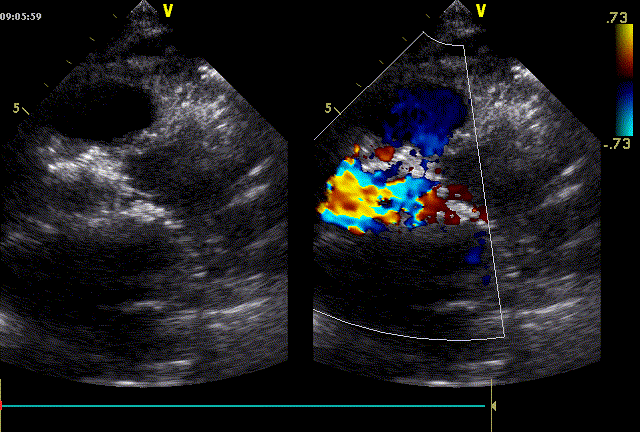

近日,中国人民解放军南部战区总医院王显悦教授、张本教授团队应用J-VALVE瓣膜完成一例高难度经心尖TAVI。患者为72岁男性,心脏超声示主动脉瓣重度狭窄伴轻度关闭不全,且二尖瓣中度狭窄。由于具有急性心力衰竭、高血压3级、肺气肿等其他疾病,且体重仅35公斤,对外科开胸手术耐受较差,风险极大,经过团队综合评估,决定行经心尖TAVI手术,拟植入25mm J-VALVE瓣膜。该患者存在升主动脉瓷化和左室流出道重度钙化,为手术增加了额外难度,术者团队凭借过硬的专业技能和细节处理能力,有效避免了术中可能存在的风险,并成功植入瓣膜。术后食道超声示无瓣周漏、无冠脉堵塞等并发症,患者症状明显缓解,手术顺利完成。

心脏超声示:主动脉瓣重度狭窄伴轻度关闭不全;二尖瓣中度狭窄伴轻度关闭不全;三尖瓣轻度反流;心包积液(少量)。

术后总结